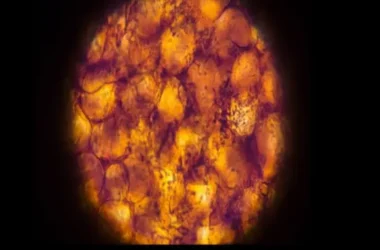

يشكل قاع الحوض شبكة معقدة من العضلات والأربطة التي تمتد من عظم العصعص في الخلف إلى عظم العانة في الأمام. هذا التكوين الحيوي يعمل كدعامة طبيعية تدعم أعضائك الحيوية، مثل المثانة والأمعاء والرحم (لدى النساء).

عندما تكون هذه العضلات قوية ومرنة، فإنها تحافظ على الأعضاء في مكانها الصحيح وتضمن عملها بكفاءة. على النقيض، يؤدي ضعف هذه العضلات إلى تحرك الأعضاء من مكانها الطبيعي أو هبوطها، مما يعيق أداءها السليم ويسبب مشكلات صحية مختلفة.